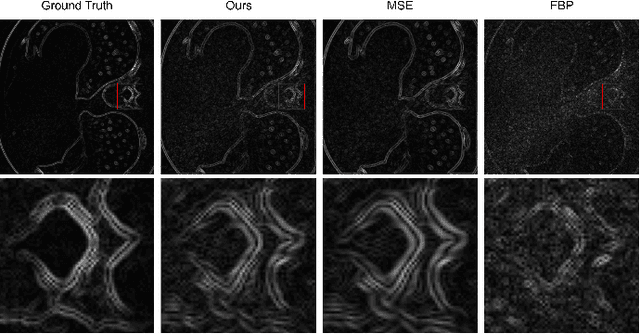

Abstract:Computed Tomography (CT) image reconstruction is crucial for accurate diagnosis and deep learning approaches have demonstrated significant potential in improving reconstruction quality. However, the choice of loss function profoundly affects the reconstructed images. Traditional mean squared error loss often produces blurry images lacking fine details, while alternatives designed to improve may introduce structural artifacts or other undesirable effects. To address these limitations, we propose Eagle-Loss, a novel loss function designed to enhance the visual quality of CT image reconstructions. Eagle-Loss applies spectral analysis of localized features within gradient changes to enhance sharpness and well-defined edges. We evaluated Eagle-Loss on two public datasets across low-dose CT reconstruction and CT field-of-view extension tasks. Our results show that Eagle-Loss consistently improves the visual quality of reconstructed images, surpassing state-of-the-art methods across various network architectures. Code and data are available at \url{https://github.com/sypsyp97/Eagle_Loss}.